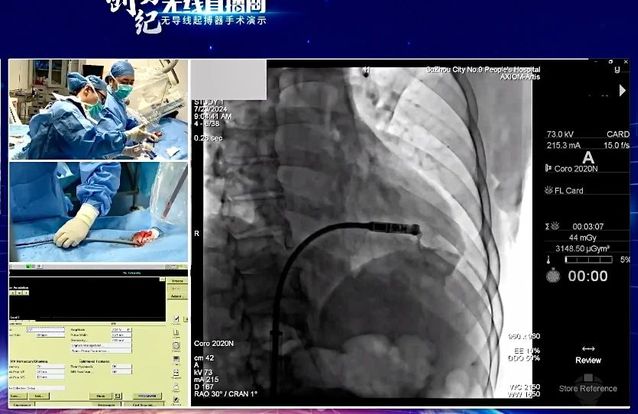

7月24日,“创势纪·无线直播间—苏皖区域无导线起搏器手术演示”在线上举行,探花直播 心血管内科主任吴雁鸣参与手术演示,助力提升区域心血管病防治水平。本次活动由江苏省医学会心血管病学分会副主任委员、苏州市心血管病学分会主任委员、苏州大学附属第一医院心内科主任蒋廷波主持,汇聚了一大批专家教授开展手术演示和线上探讨,通过学术交流积极推动苏皖地区心血管病防治水平的进一步提高。

早在2021年,探花直播 心血管内科就积极引入和开展无导线心脏起搏器植入术,是我区首家成功独立开展无导线起搏器植入手术的医院。心血管内科主任吴雁鸣是我区首位独立无导线起搏器术者,目前已成功独立植入近30例,受益人群大多为高龄老人,其中年龄最大的患者接受手术时已经103岁。

这一技术的成熟推广,对区域患者健康有着重要意义。植入心脏起搏器主要针对严重缓慢性心律失常的患者。传统的心脏永久起搏器由脉冲发生器和电极导线组成,医生通过腋静脉或锁骨下静脉将起搏器电极导线送至右心房或右心室,在患者胸前区胸大肌处制作与起搏器大小合适的囊袋,以容纳脉冲发生器。无导线起搏器不同于传统起搏器的地方在于:它不需要使用导线将脉冲发生器连接到起搏电极上。相反,它将脉冲发生器和起搏电极集成在一起,以微缩胶囊的形式直接植入患者的心腔内部。